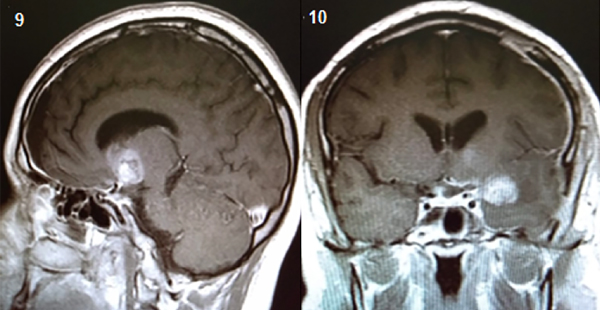

Para el análisis anátomo-patológico, se enviaron múltiples fragmentos irregulares de tejido que medían de entre 3,8 cm y 0,5 cm de diámetro máximo, los cuales revelaron al examen microscópico una proliferación de células neoplásicas de estirpe germinativo constituida por dos componentes: uno de ellos caracterizado por células con núcleos redondos, hipercromáticos, ligeramente irregulares con citoplasmas claros y amplios dispuestos en nidos sólidos, surcados por finos ejes fibroconectivos vascularizados con presencia de acúmulos linfocitarios;  el segundo componente presentaba elementos teratomatosos maduros, en sectores inmaduros, derivados principalmente de la capa mesodérmica y endodérmica. A nivel de esta última se destacaban características atípicas y áreas necrohemorrágicas.

En base a los hallazgos antes descriptos se arribó al diagnóstico de Neoplasia de células germinales mixtas: Germinoma (35%) y Teratoma con áreas Inmaduras y transformación carcinomatosa (65%),(Figura 11 y 12).

Figura 11: Teratoma con características atípico.